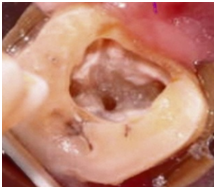

Access cavity preparation was performed under local anaesthesia of 2% lignocaine with 1:2,00,000 epinephrine. Inflamed pulpal tissues located in the pulp chamber were removed and internal anatomy revealed 3 main root canals: mesiobuccal (MB), distobuccal (DB), and palatal (P).Later DG 16 endodontic explorer was used to explore any additional canals. A small haemorrhagic point was noticed around 3-4mm mesial to the main palatal canal indicating a second palatal canal. The regular triangular access cavity shape was modified to a trapezoidal shape in order to gain proper access to the additional canal. The pulp was extirpated, and working lengths of each canal were determined by means of an electronic apex locator (Root ZX; J Morita) and then confirmed by a radiograph (Figure 2). Initial instrumentation of the canals was done with #10 SS files (Dentsply Maillefer).Canal instrumentation and debridement were carried using the crown-down technique with Protaper Rotary files(Dentsply/Maillefer). Apical preparation was performed till F1 for MB, DB canals and F2 for MP and DP canals (Figure 3). Canals irrigated using 2.5% NaOCl and EDTA, access temporized with ZOE cement and appointment was concluded.

Figure 3 Clinical examination showing 4 root canal orifices: 2 buccally and 2 palatally (mirror image).

Variations in morphology and anatomy, although uncommon can occur in any tooth. The tooth described in this case report is maxillary third molar which had two separate palatal roots, each with a distinct root canal. The majority of endodontic literature describes the maxillary molars as having 3 roots with 3 or 4 root canals.12 The prevalence of 2 palatal roots in maxillary molars is rare and the presence of 2 separate buccal and palatal roots with distinct orifices and foramen is very rare. Whenever indistinct images of palatal roots are presented in preoperative x-ray images taken at different angulations, the clinician should interpret the possibility of two palatal roots and the access cavity is thereby modified accordingly to gain proper instrumentation of the additional canal.13 Shape of access cavity is variable, depending upon the canal configuration, thorough knowledge and properly designed pulp cavities help the clinician to locate and negotiate the root canalanatomy.14 In the present case, the access cavity is made slightly wider palatally in order to accommodate the second palatal canal found mesially thereby converting the conventional triangular access form to trapezoidal (Figure 3). One to three rooted maxillary third molars are more common.15 However, the number of roots/canals in maxillary third molar varies from one to five.16 Sidow et al.10 showed that 15% of maxillary third molars had only one root, 32% had two roots,45% had three roots, where as 7% had four roots. Tomazinho et al.17 reported an unusual case of a maxillary first molar with two palatal roots. Pecora et al.18 showed that 68% had three canals and 34 % had four canals. Stropko19 showed that 60% had three canals, 20% had four canals and 20 % had two canals only.